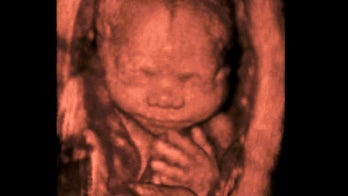

May 26, 2021 Group launches $2M TV campaign to highlight the humanity of unborn children EXCLUSIVE: An anti-abortion group is pouring an initial $2 million into a campaign they say will "highlight the humanity of unborn children" as the Supreme Court prepares to hear a case that critics say could undercut Roe v. Wade.